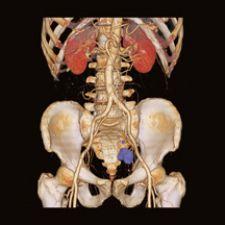

Dr. Kwee has explored a new investigational imaging agent for cancer using Philip’s Gemini TF 64 PET/CT system. The Gemini TF 64 has “TruFlight” PET technology, which is Time-of-Flight reconstruction for short scan times and high image quality. Dr. Kwee explained, “We have had experience with fluorine-18 fluorocholine, which is an investigational tracer at the moment. While the jury is still out for the tracer, it does seem better than fluorodeoxyglucose for detecting some cancers, particularly prostate cancer. One nice thing about this tracer is that it is taken up by tissues faster than fluorodeoxyglucose, which means imaging can be performed right after injection. With fluorodeoxyglucose, patients have to wait at least one hour after tracer injection before the actual PET/CT scan is performed.”